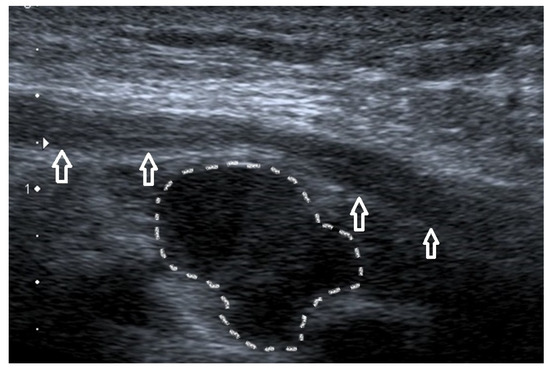

4.8. Epitrochlear Lymphadenopathies